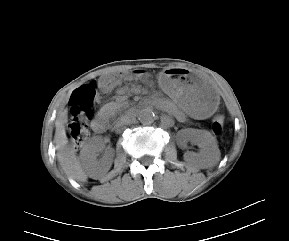

标题: CT19533:病变来源于哪?

患者,男,发现上腹部包块两月余。

病变位于肝胃间隙,实际就是位于小网膜囊(左肝下后间隙),呈轻度不均匀性强化,腹腔内及腹膜后见多发肿大淋巴结。所以我考虑肝胃间隙恶性胃肠间质瘤并淋巴结转移。

病灶强化不显著,灶周及腹膜后见多量淋巴结肿大,考虑淋巴瘤可能,其次考虑间质瘤

强化后病变与胃壁分界清楚,并且血供不是来源胃壁血管。考虑胰腺颈体癌并腹腔腹膜后淋巴结转移。